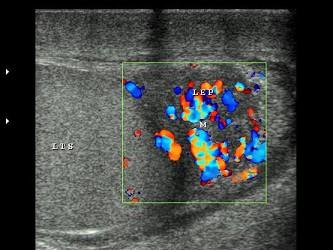

问题 男性,阴囊肿大,表皮温度高,触痛明显,超声见附睾尾体积增大,CDFI:血流信号丰富,如图所示,考虑为 ?(?)

选项 A.附睾炎 B.睾丸炎 C.附睾结核 D.睾丸结核 E.精索静脉曲张

答案 A